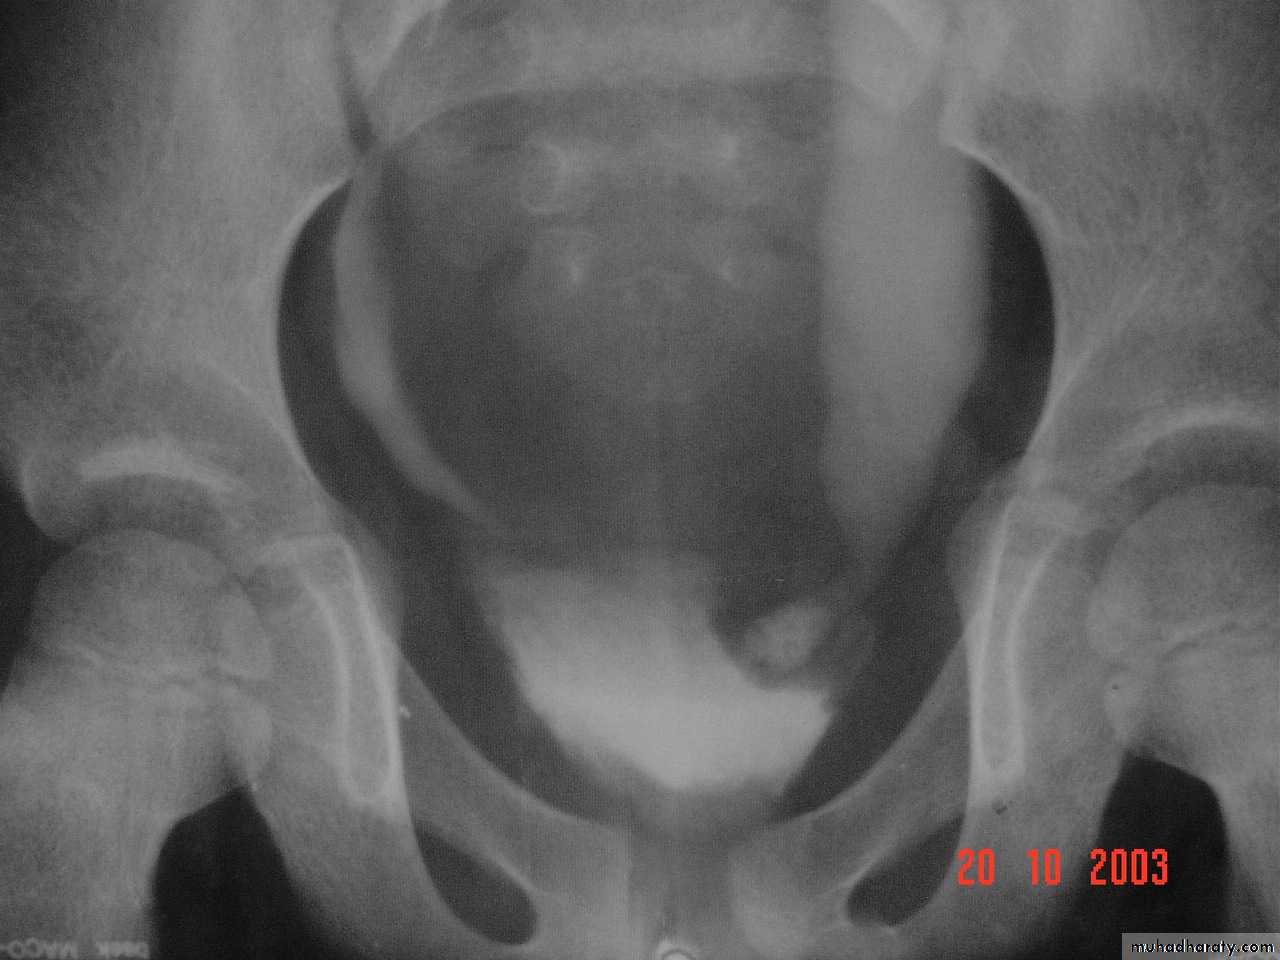

34- vesico-uretric junction stone (CT scan)